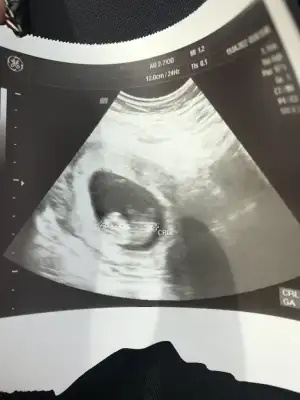

Merhaba 12+5 haftalik, sizce ne olabilir, gecen sormustum size erkek demistiniz, doktor kiz olabilir dedi ama net konusmadi, belli degil henuz tam dedi, sormak istedim🙈size yeniden😊

Karindan ultrason bu arada